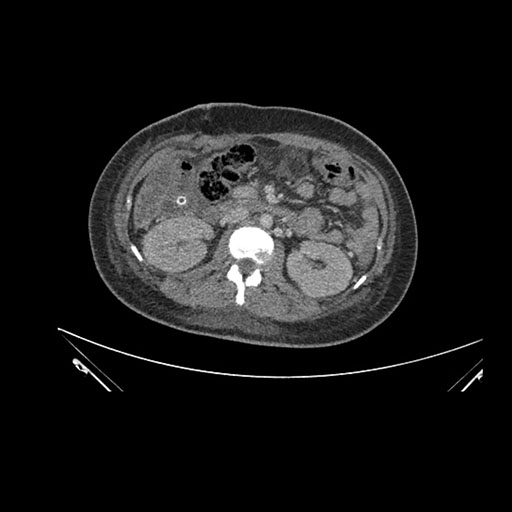

Imaging Analysis

Look through the patient's CT scan to identify any areas of concern for the necessary procedure.

Axial Arterial

Based on initial findings, which issue(s) would you be most concerned about?